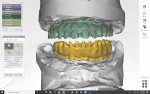

After all the layers were merged by the planning center, the clinician could perform bone contouring and implant planning. For the maxilla, to hide the transition zone, bone needed to be reduced in height. As depicted in Figure 9 through Figure 11, reduction of bone height in the area of tooth No. 8 would enhance implant placement as this would also increase bone width. The blue line in Figure 11 indicates bone level was around 13 mm from the incisal edge of tooth No. 8. For the mandible, to hide the transition zone, the bone needed to be reduced to approximately 18 mm from the incisal edge of tooth No. 27 (Figure 12 through Figure 14). The maxillary and mandibular All-on-4® implant rehabilitation was enabled via adequate restorative space in this patient (Figure 12 through Figure 14) and would replace the missing hard and soft tissues and hide the transition zone behind the lips.15-17

The laboratory needed to make individual crowns that fit over the framework, so they opted to "split" the whole design into crowns and base in the design software (Figure 22 and Figure 23). Even in the gingiva, cutback could be pre-determined.